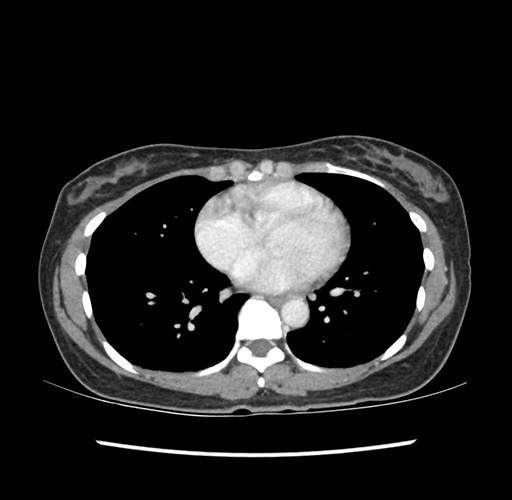

Imaging Analysis

Look through the patient's CT scan to identify any areas of concern for the necessary procedure.

Based on your CT findings, which issue(s) would give reason for "planned slowing down moment(s)" in this case?